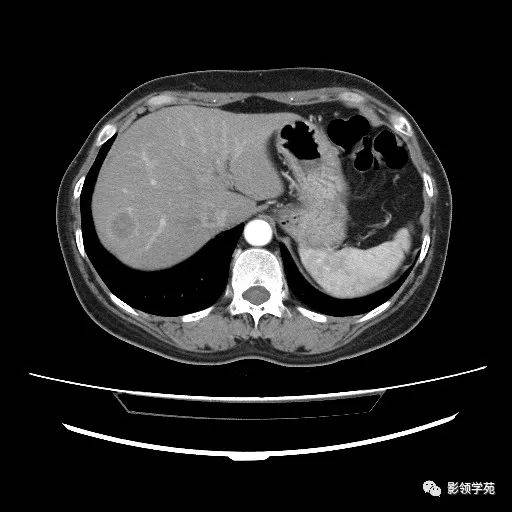

肝转移瘤

图22 肝转移瘤